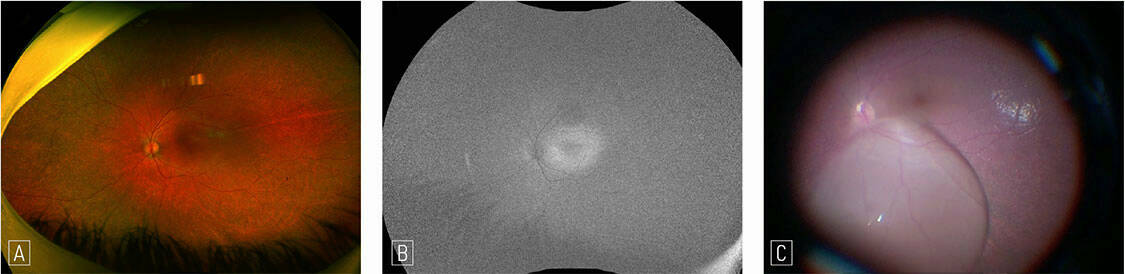

Figure 4. Décollement de rétine chez un patient atteint d’un glaucome congénital et prise en charge chirurgicale. A. Opacités du segment antérieur liées au glaucome, rendant difficiles l’examen du fond d’œil et la chirurgie. B. Photographie peropératoire : décollement de rétine total. C. Photographie peropératoire : déhiscence périphérique responsable du décollement de rétine. D. À 3 mois postopératoires, la rétine est à plat sous tamponnement par huile de silicone.